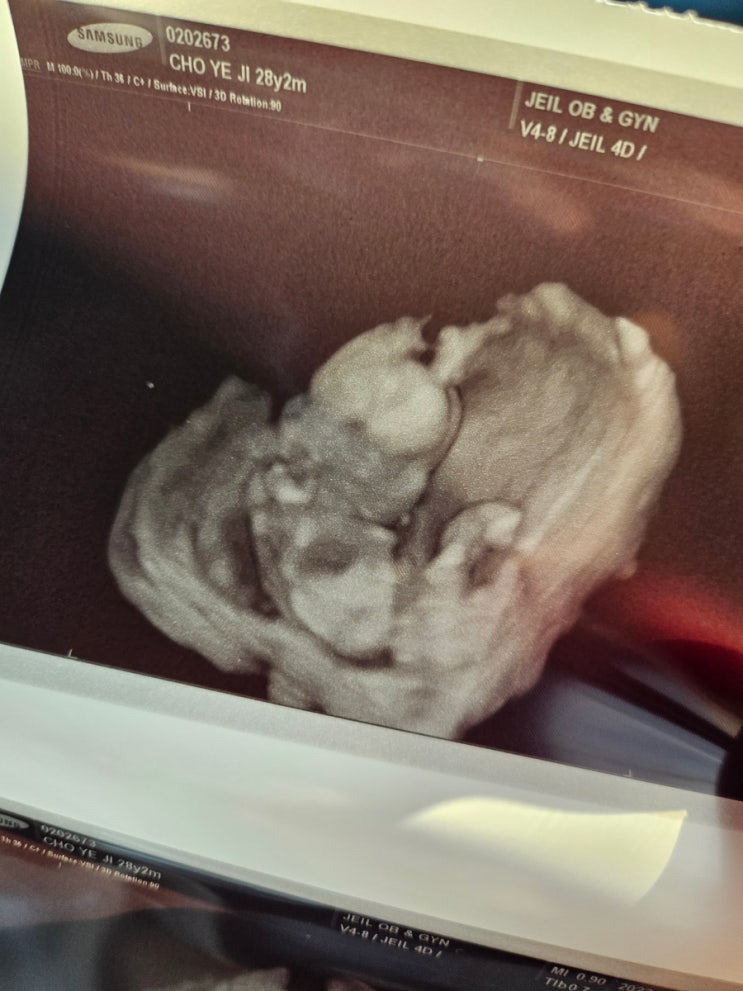

[임신16주] 2차 기형가 검사/성별확인